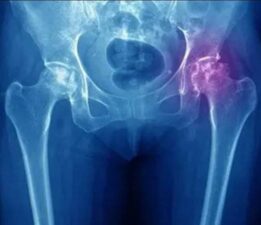

Kalça avasküler nekrozunda erken teşhisin önemi

Ortopedi ve Travmatoloji Uzmanı Doç. Dr. Recep Kurnaz, kalça avasküler nekrozu hakkında önemli bilgiler verdi. Kalça avasküler nekrozu, kalça kemiğinin kan akışının azalması veya tamamen kesilmesi nedeniyle oluşan bir durumdur. Doç. Dr. Kur...